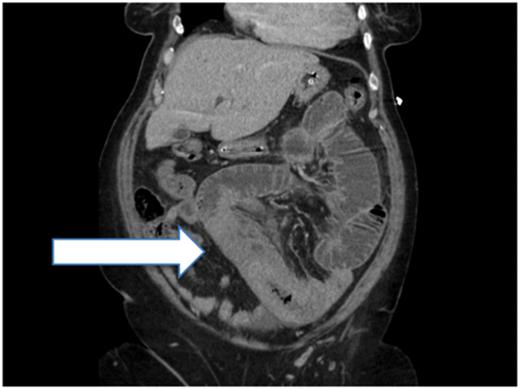

A CT scan was performed that showed dilation of the proximal small bowel, with a long segment of thickened small-bowel loops that was reported as possible intussusception (Fig. 2). The images were discussed further at the multidisciplinary surgical radiology meeting in the context of her haematology results. It was determined that the long segment of the thickened small bowel was, in fact, haemorrhage rather than intussusception.

Post-contrast CT (sagittal plane) showing proximal small-bowel dilation and a thickened small-bowel segment (Case 1).